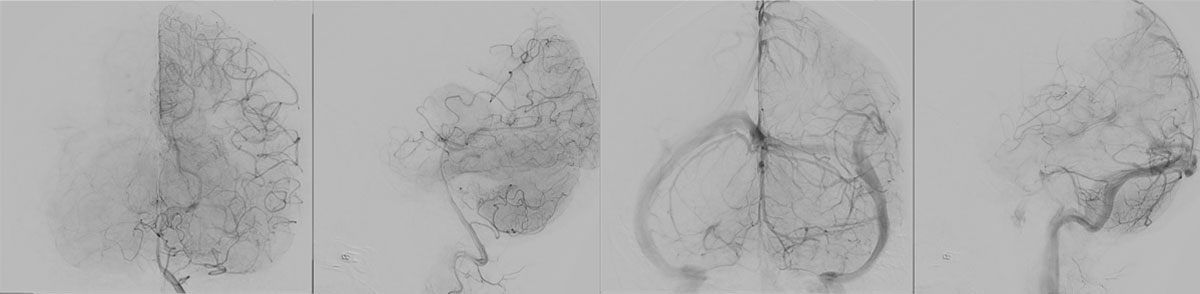

6 months DSA follow up